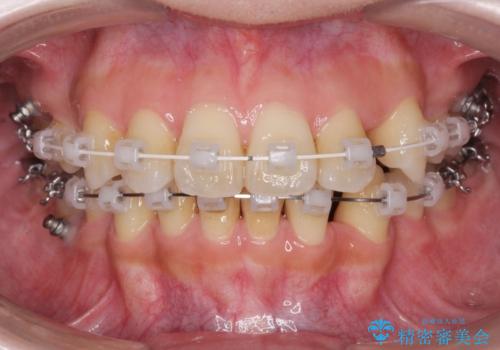

八重歯を矯正治療で治したい!

- 八重歯・がたつきのある歯並びの改善を求めて来院されました。

全部の歯が入り切るスペースがなかったため、小臼歯4本を抜去しワイヤーを用いたマルチブラケット矯正を選択しました。

歯並びの改善と共に、歯ブラシがしやすくなった!と喜んでいただくことができました。